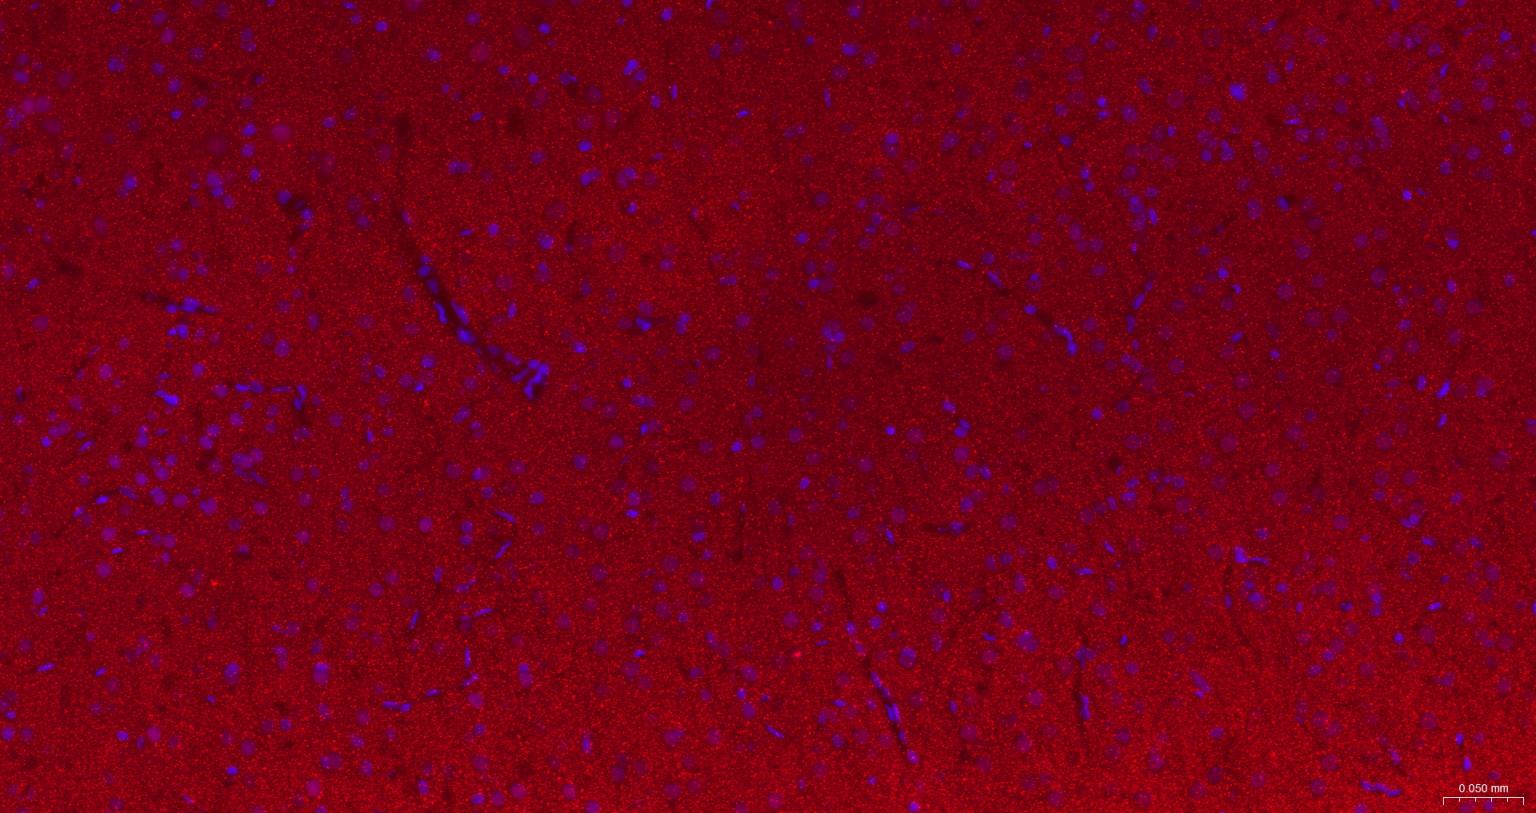

Paraformaldehyde-fixed, paraffin embedded Rat Cerebrum; Antigen retrieval by boiling in sodium citrate buffer (pH6.0) for 15 min; The section was incubated with Alpha Synuclein Monoclonal Antibody, Unconjugated (bsm-54277R) at 1:200 overnight at 4°C. Followed by conjugated Goat Anti-Rabbit IgG antibody (Red, bs-0295G-BF594), DAPI (blue, C02-04002) was used to stain the cell nuclei.